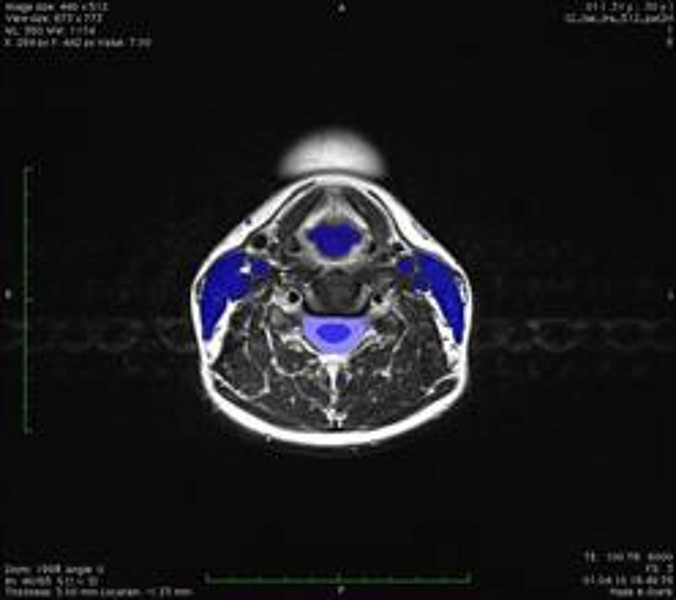

Mögliche Anwendungsziele sind z. B. Lymphknotenexstirpationen am Hals zum Ausschluss oder zur Diagnosesicherung eines malignen Prozesses. Teilprojekte sind u.a. die Erhebung anatomischer Daten durch Segmentierung von Hals-MRT’s in verschiedenen Kopfpositionen und die Erstellung eines daraus abgeleiteten mathematischen Modells. Des Weiteren soll ein flexibles Sonographie- und MRT-geeignetes Halsphantom konzipiert und verwirklicht werden, um das Navigationssystem evaluieren zu können.